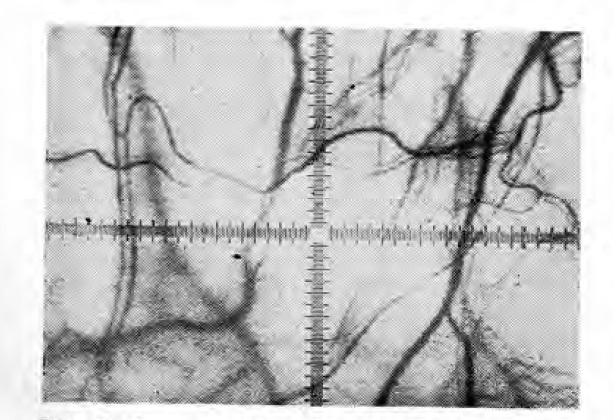

При обычном фотографировании через щелевую лампу с помощью микрофотонасадки изображение градуированной шкалы на фотографиях не получается из-за несовпадения фокусов. Чтобы устранить этот недостаток мы предлагаем производить фоторегистрацию аппаратом (рис. 1), объектив которого соединен с окуляр-микро- метром щелевой лампы. Для этого необходимо изготовить переходное кольцо (рис. 2), оно имеет наружную резьбу для соединения с резьбой объектива фотоаппарата, предназначенной для светофильтра, и внутреннюю резьбу 2 для соединения с окуляр-микрометром щелевой лампы. В целях более удобного ввинчивания переходного кольца в объектив фотоаппарата существуют 4 выемки 5. Переходное кольцо предназначено для фотографирования фотоаппаратом «Зенит- ЕС» с объективом типа «Индустар-50». В процессе микрофотографирования в качестве дополнительного освещения применялась фотовспышка «Чайка». Использовалась черно-белая фотопленка чувствительностью 65 ед. ГОСТ. На микрофотоснимках хорошо просматриваются микрососудистый рисунок и градуированная шкала окуляр-микрометра (рис. 3).

Рис. 3. Фото сосудов конъюнктивы глазного яблока с изображением крестообразно градуированной шкалы X 35.